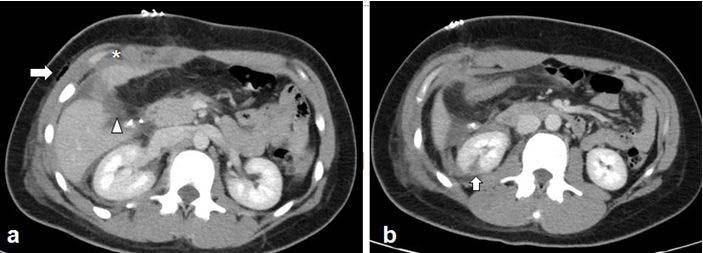

image: Images in a 27-year-old female victim was stabbed in the right mid abdomen by her boyfriend. (a) Axial abdomen CT scan demonstrates an AAST (American Association for the Surgery of Trauma) grade 2 liver laceration (arrowhead) with a small perihepatic hematoma (asterisk), and subcutaneous emphysema (arrow) at the site of stab injury. (b) Additional axial CT abdomen image demonstrated irregular hypoattenuation in the inferior aspect of left kidney, representing an AAST grade 2 laceration. The patient underwent surgical repair of liver laceration and cholecystectomy. The renal injury was managed conservatively.

"During the pandemic, victims experienced more injuries to the chest and abdomen compared to prior years," said coauthor Babina Gosangi, M.D., assistant professor of radiology at Yale New Haven Health in New Haven, Connecticut, and former emergency radiology fellow at Brigham and Women's Hospital. "For instance, one victim sustained multiple bilateral rib fractures with right pneumothorax and bilateral lung contusions--requiring hospital admission for more than 10 days--after she was repeatedly punched in the chest. Another victim was stabbed in the abdomen and had lacerations to the liver and kidney."